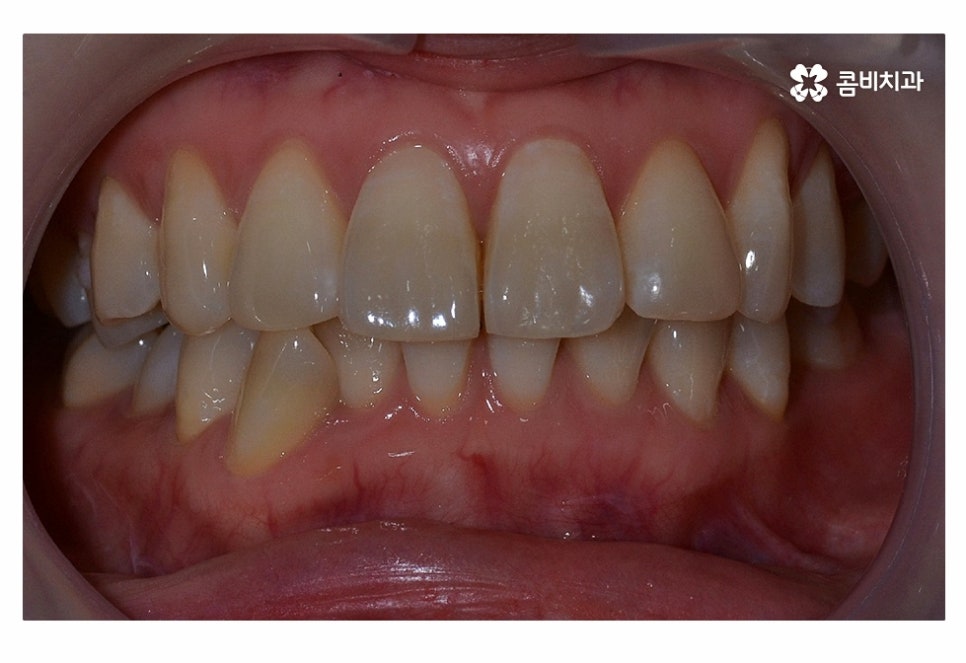

사진으로 보시는 환자분의 경우 윗니에 비해

아랫니가 좀 더 불규칙하다는 것을 알 수 있는데요.

위 환자분 또한 심미성을 중요시하였으나 아랫니까지

설측으로 할 경우 발음이 불편할 수 있다는 단점으로 인하여

아랫니의 경우 순측으로 장치를 부착하였고 아랫니의 경우

순측으로 장치를 부착해도 크게 웃지 않는 이상 잘 보이지 않기 때문에

위 환자분처럼 윗니만 치아설측교정으로 진행을 하고 아랫니는

순측으로 진행하는 경우가 많이 있어요.